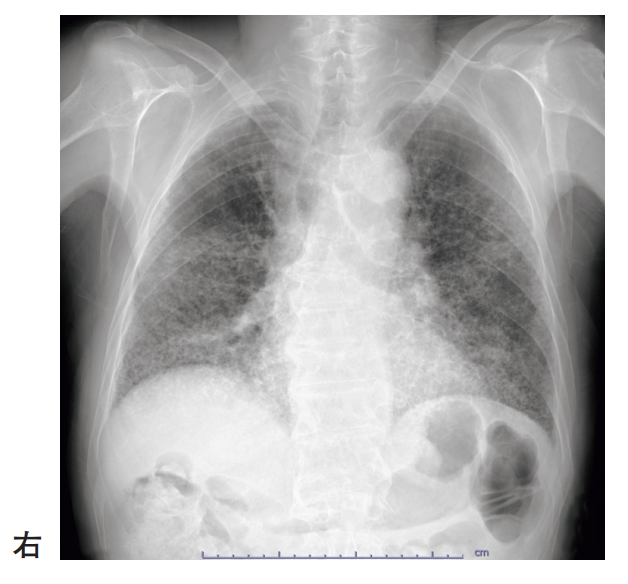

73歳の女性。胸部単純エックス線写真を別に示す。

考えられる疾患または状態はどれか。